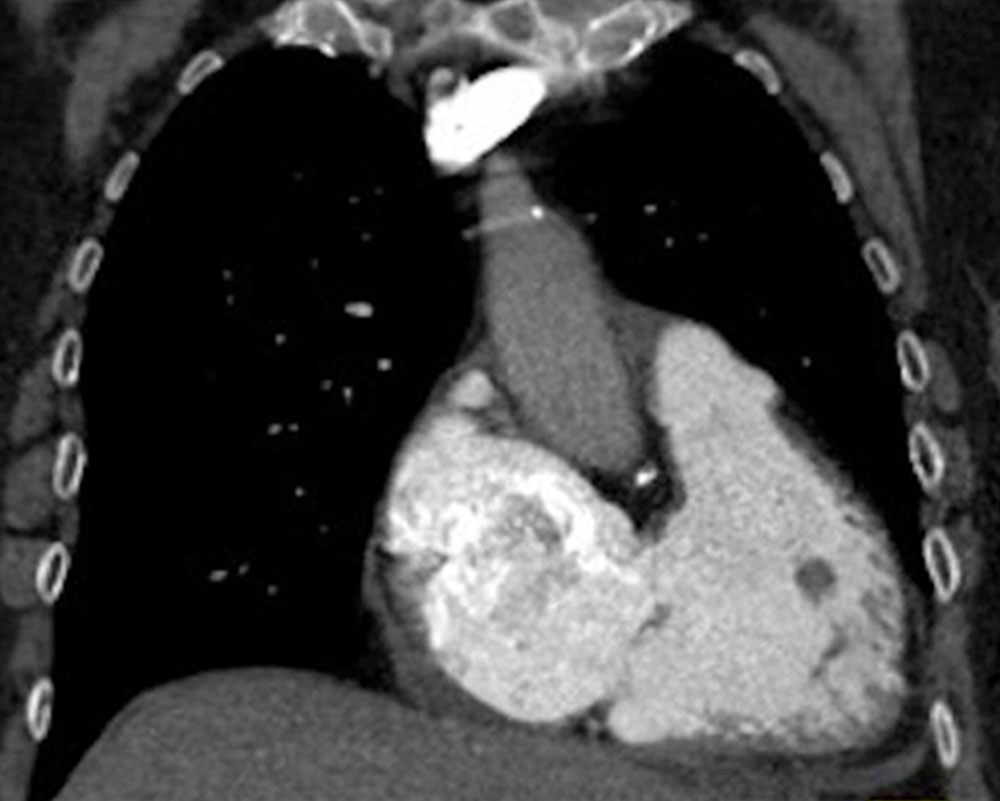

The most important, because most dangerous, complication of phlebothrombosis is the dislodgement of the thrombus via the draining veins (thromboembolism) to the central circulation. This may then lead to mechanical blockage of central vessels by the thrombus with localized thrombosis. Even more centrally after passage through the vena cava and the right heart, this blockage then affects the pulmonary arterial pathway, which is partially or completely occluded by thrombus, resulting in pulmonary embolism.

Pulmonary embolism can be sudden and prominent with massive clinical symptoms, including circulatory arrest and right heart failure due to the high flow resistance. However, pulmonary embolism is often not diagnosed immediately due to unspecific or mild symptoms. In addition, it may be completely asymptomatic in the case of smaller pulmonary emboli.

In patients with larger venous malformations who have recurrent smaller thromboembolism into the pulmonary circulation over a long period, the pulmonary arteries often become slowly and progressively occluded over a period of years with increasing flow resistance and high pulmonary arterial pressure. Chronic thromboembolic pulmonary arterial hypertension (CTPAH) may develop as a result. This complication must be avoided by adequate therapy.